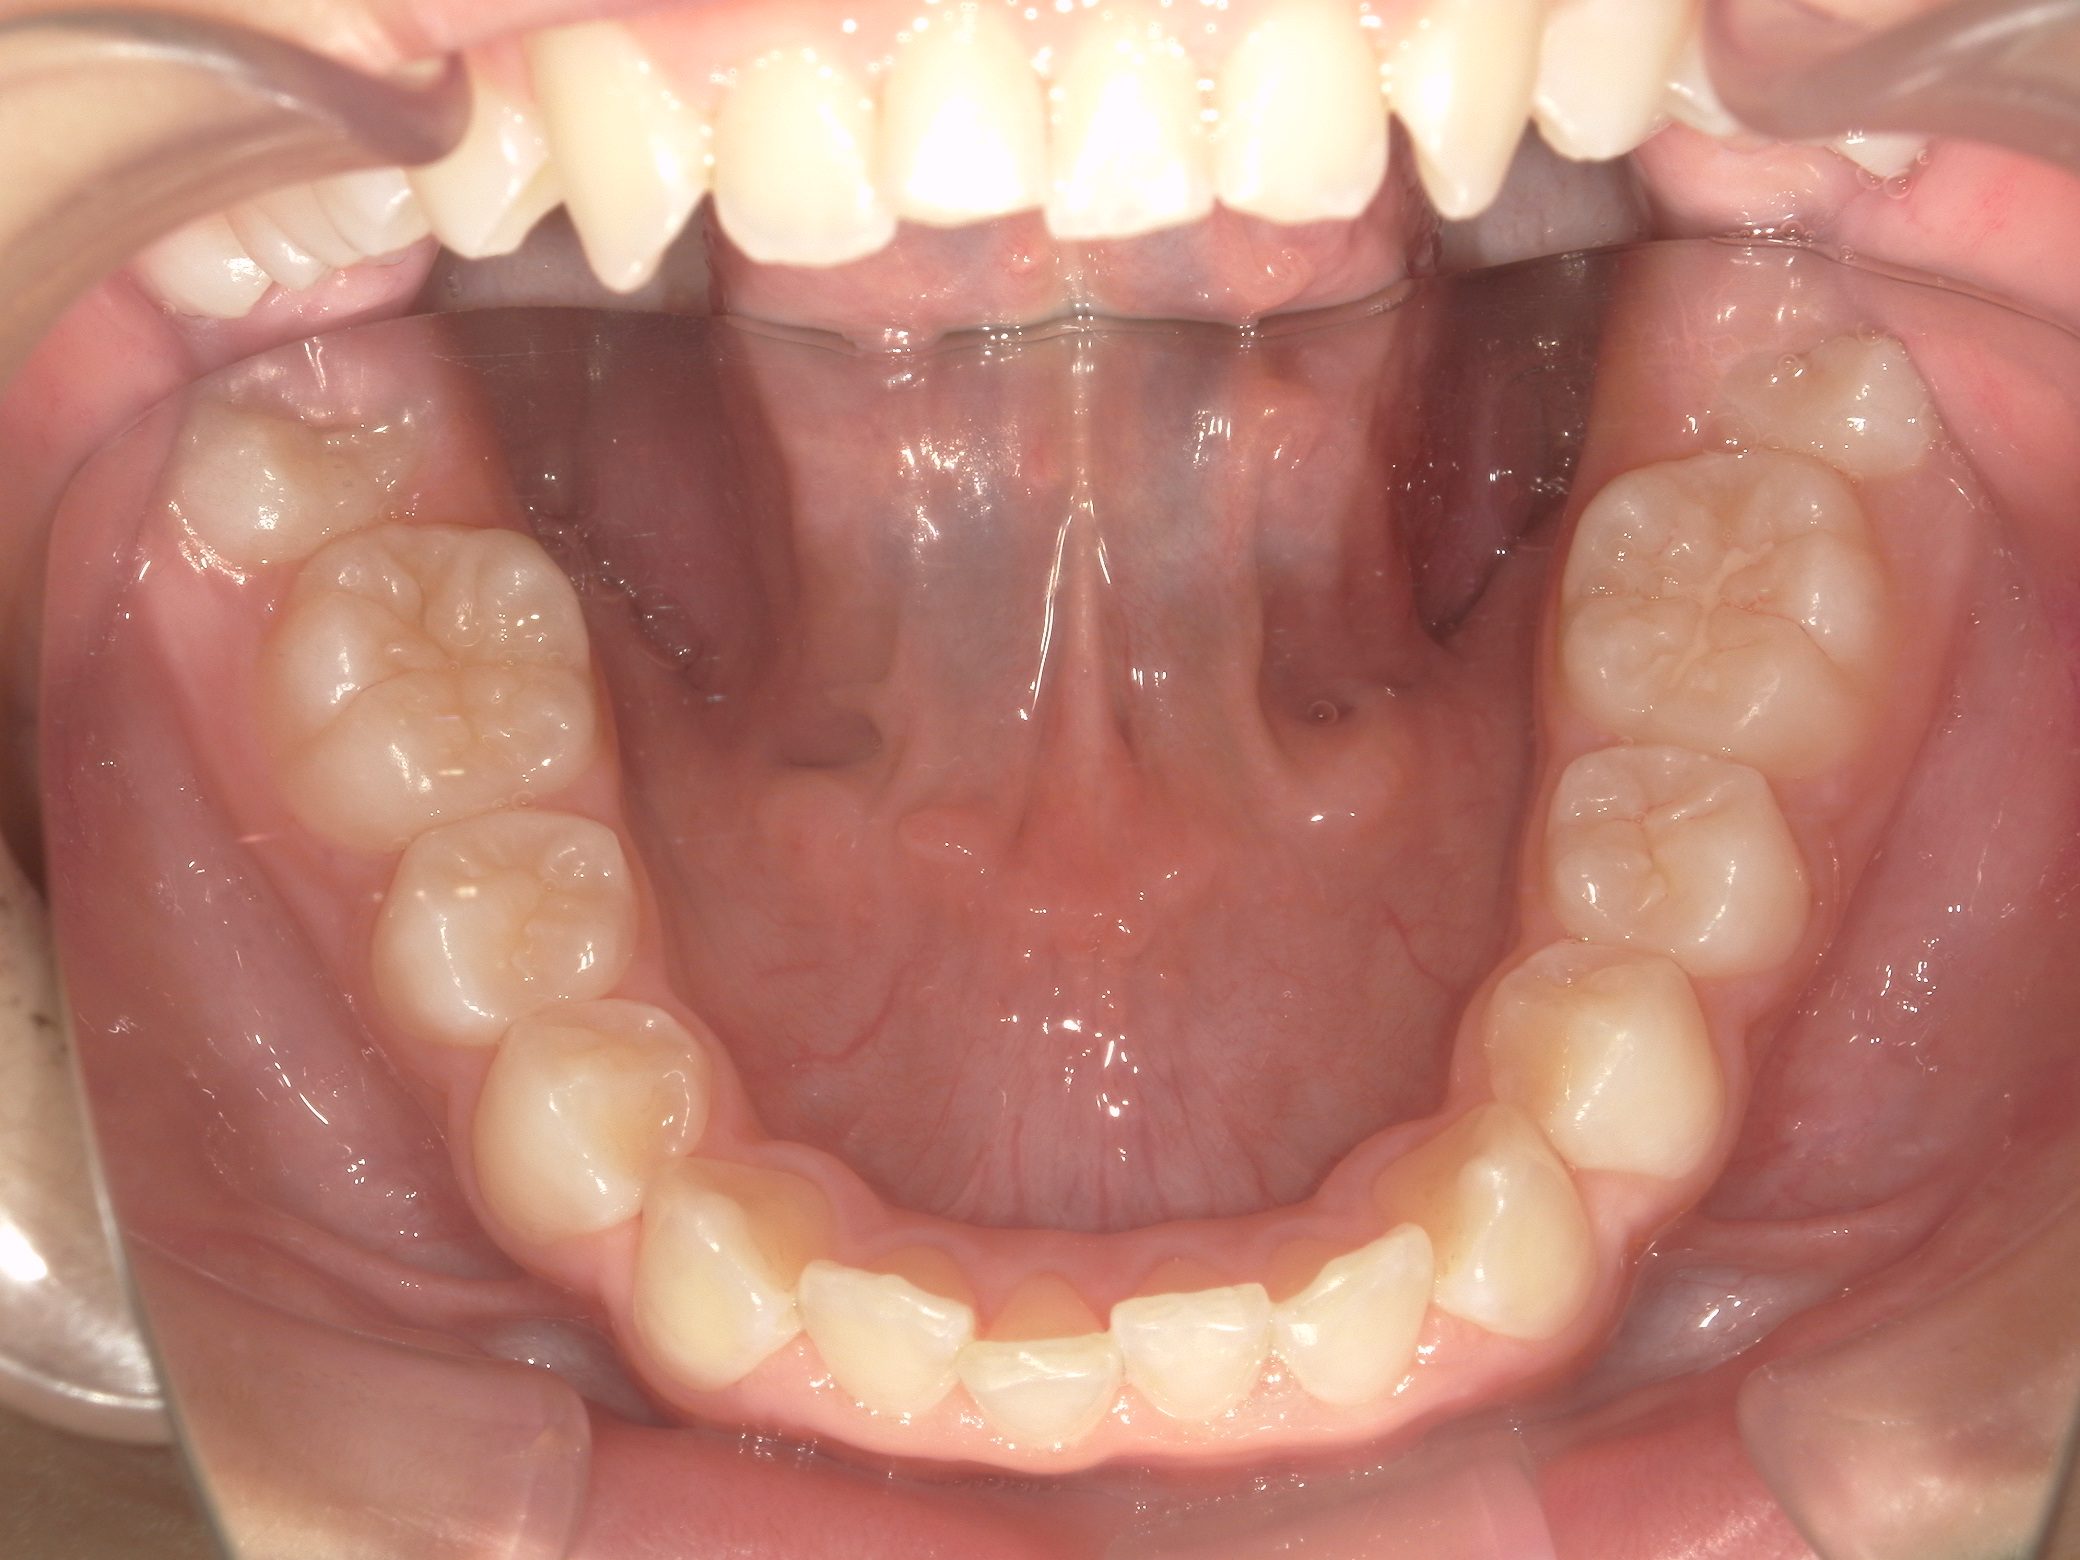

Before

After

【小学生】10歳 マイオブレース矯正 叢生(でこぼこ)と過蓋咬合(深い咬み合わせ)を改善

かなりきちんと取り組んでくれたので、機能矯正装置と MFT(筋機能療法)のみで 改善しています。

機能矯正装置のみで改善するかどうかは もともとの歯並び + 患者さんの装置の使用状況 MFTへの取り組み状況により

変わります。